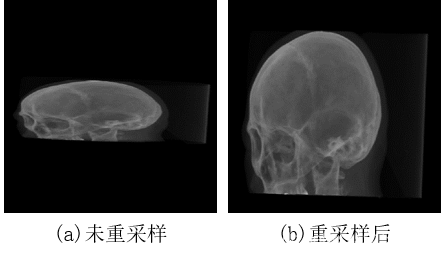

x = 5, y = 3, z = 6 a = 0.5, b = 0.1, c = 0例子,一个尺寸为512·512·83的CT序列,扫描间隔为(0.6523, 0.6523, 2.5000)mm,重采样后尺寸为512·512·315。如下图所示,